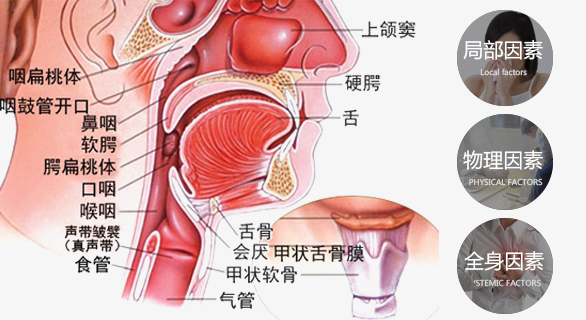

扁桃体炎 耳鼻喉科 咽炎 口咽喉癌 鼻png图片素材免费下载 图片编号

喉癌预防 咽喉癌的早期症状 喉癌是怎么引起的 喉癌的症状 喉癌基础